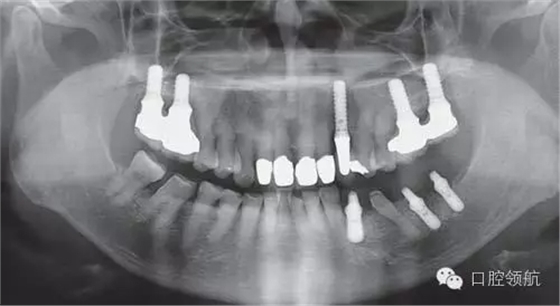

利用曲面斷層及CBCT檢查埋入部位情況,雖未出現與主訴相關的神經損傷,但無意中卻發(fā)現了種植體的舌側穿孔(圖1、圖2)。

圖1 術后的曲面斷層影像。